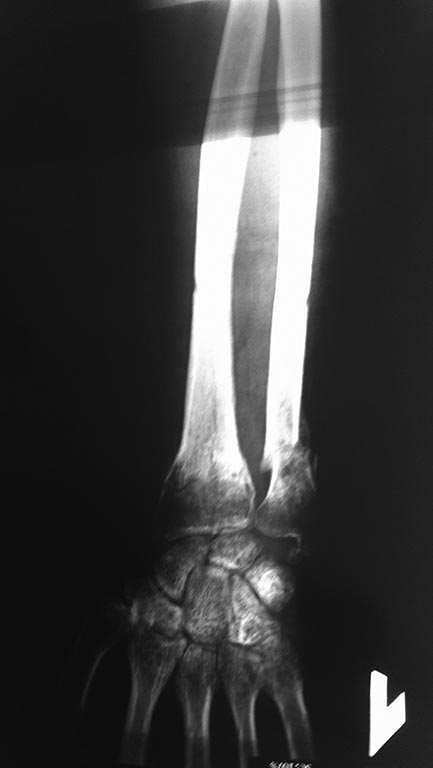

Через 8 недель, после удаления конструкции